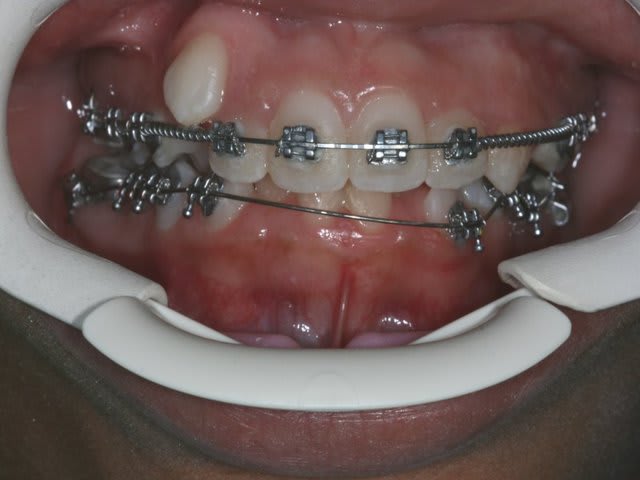

ou alors, on attends que ça devienne comme ça

Img 0477 k68wjf - Eugenol

ou encore comme ça!

à chaque fois, ça me hérisse quand les parents me répondent:

le dentiste m'a dit qu'il fallait attendre et que ça allait s'arranger

arrêter les les conseils d'autruche

Img 9861 ogyvix - Eugenol